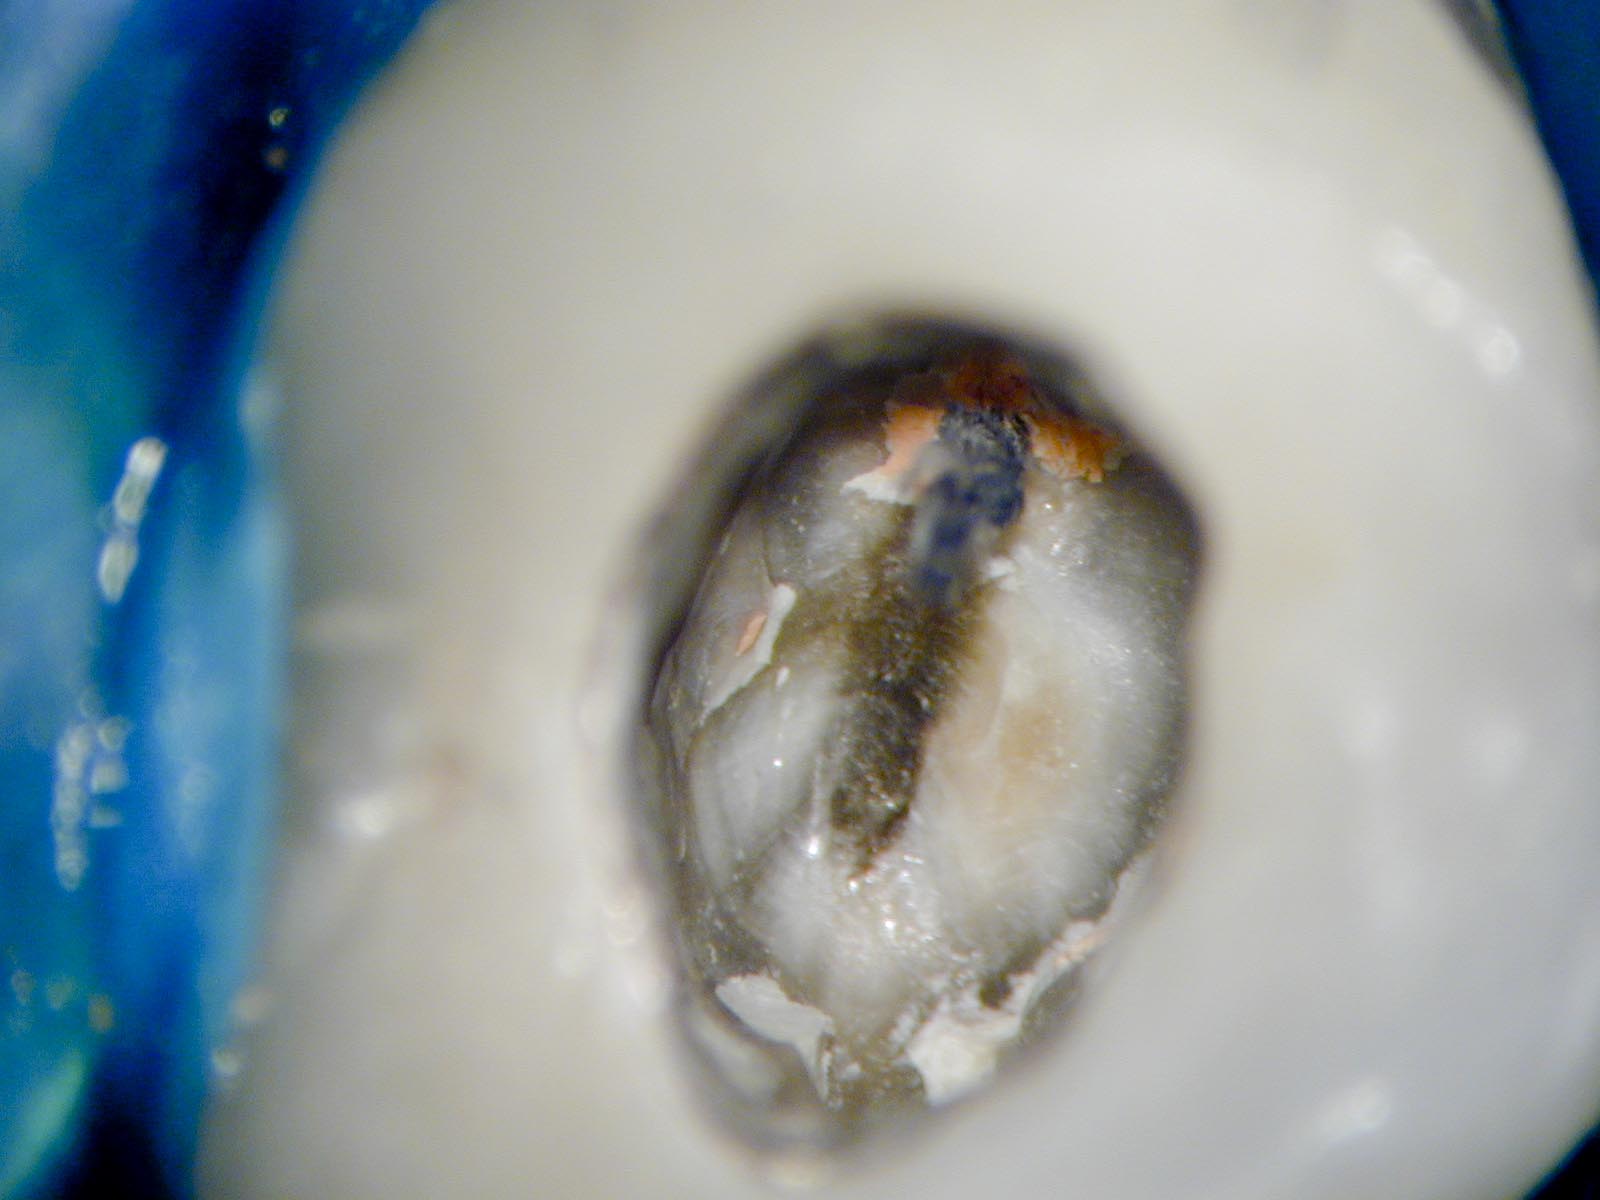

Thermafil Carrier 4

Veröffentlicht 27. April 2009 am 1600 × 1200 in Thermafil – Revision

Zweiter Wurzelkanal initial erschlossen